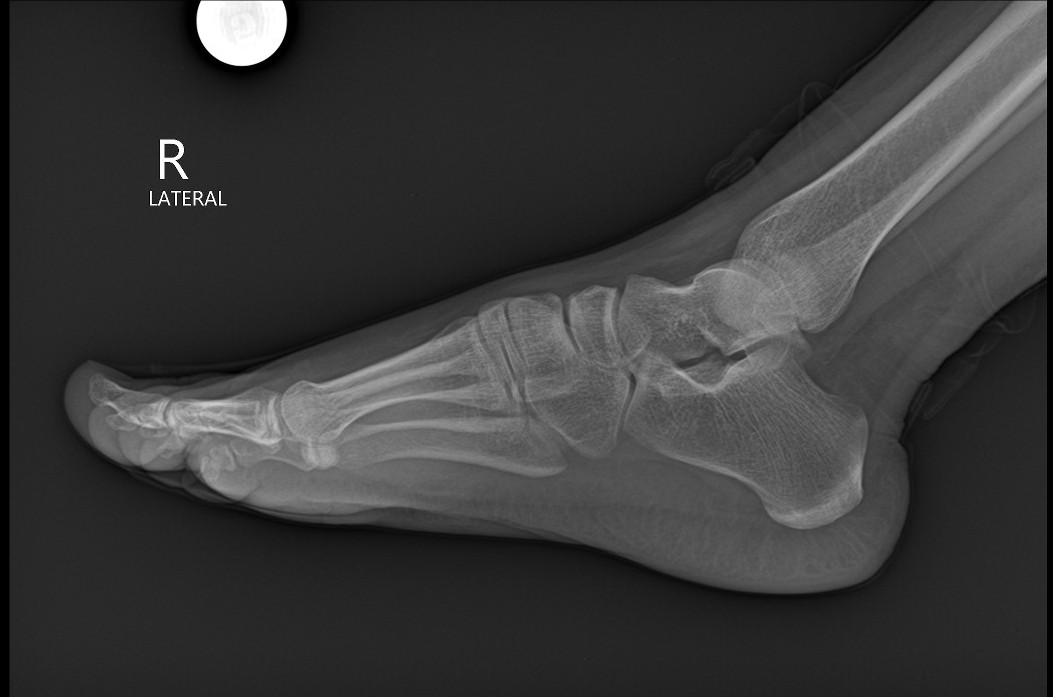

Lateral